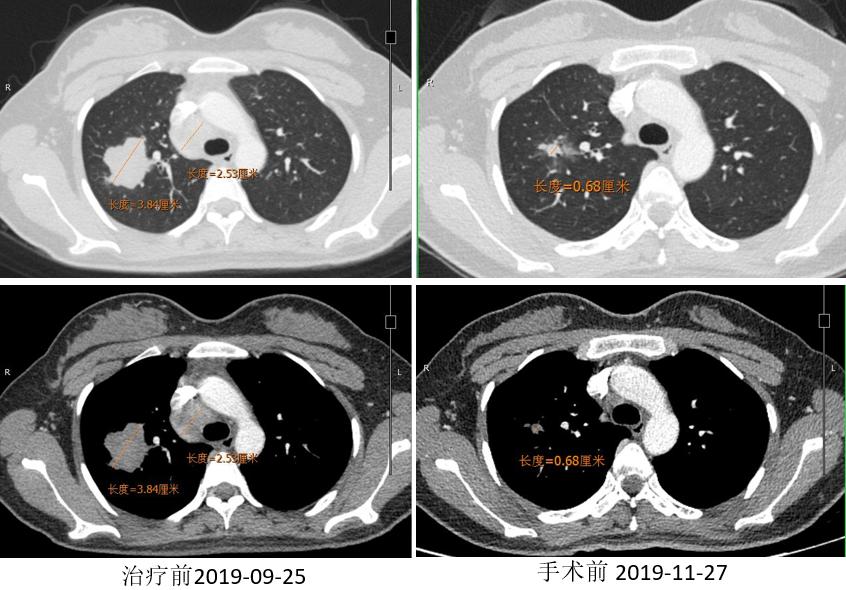

胸部CT

外周淋巴结CT